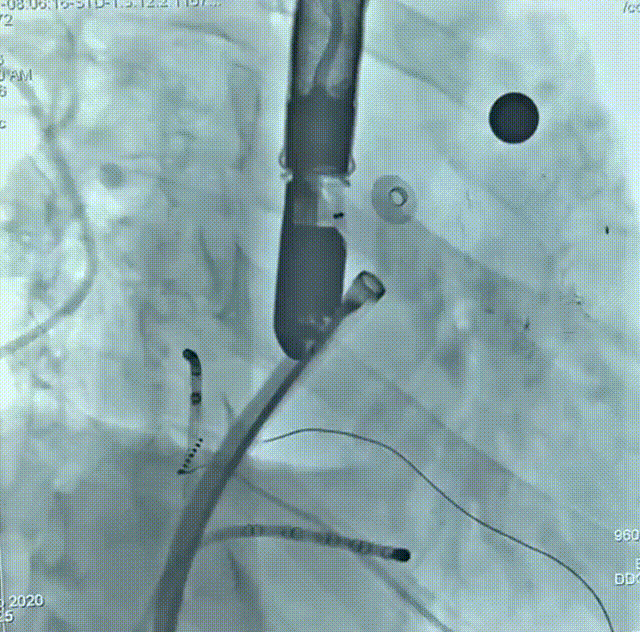

术后造影